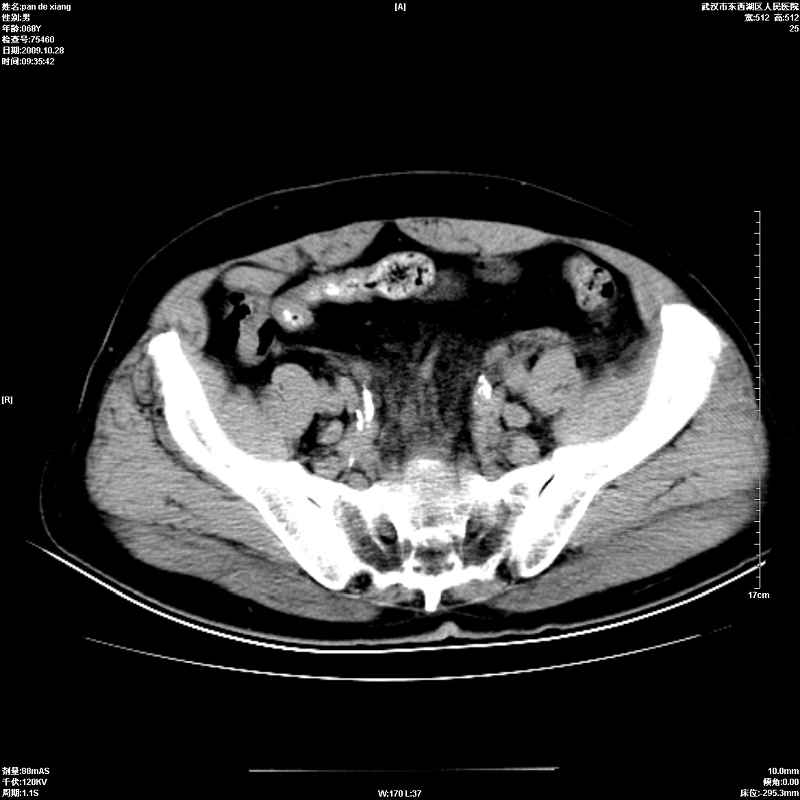

以下是引用杀毒软件在2009-10-28 20:41:00的发言:[br]结合临床考虑---白血病双肾改变或淋巴瘤。

以下是引用zxl51642在2009-10-29 9:59:00的发言:[br]结合临床“单克隆免疫球蛋白血症”,考虑双肾为继发损害并肾功能不全(尿中大量igg及少量iga、igm等大分子免疫球蛋白滤出所致继发损害),椎前软组织肿块为髓外造血。与浆细胞瘤有区别,平扫时有战友说的很清楚。